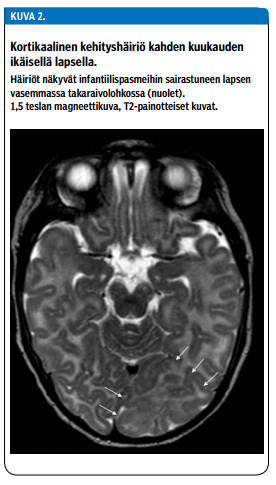

Ensilinjan etiologisiin selvittelyihin kuuluvat huolellinen anamneesi ja kliininen neurologinen tutkimus, joka sisältää arvion lapsen kehitystasosta, sekä aivojen magneettikuvaus. Näiden avulla infantiilispasmien etiologia selviää yli puolella sairastuneista (6). Lisäksi alkututkimuksiin kuuluvat veri-, virtsa- ja likvornäytteet. Ehdotetut alkututkimukset ja mahdollisia syitä infantiilispasmeille on esitetty kuviossa 1 «»3. Jos etiologia ei alkuvaiheen tutkimuksissa selviä eikä vastetta ensisijaishoidoille (ks. alla) saavuteta, edetään harkinnan mukaan geneettisiin ja aineenvaihdunnallisiin jatkotutkimuksiin. Lisäksi aivojen kuvantamisesta 3 teslan magneettilaitteella voi olla hyötyä. Esimerkiksi aivojen kuorikerroksen kehityshäiriöt (kuva 2 «»4) eivät välttämättä tule näkyviin ensimmäisissä kuvissa.